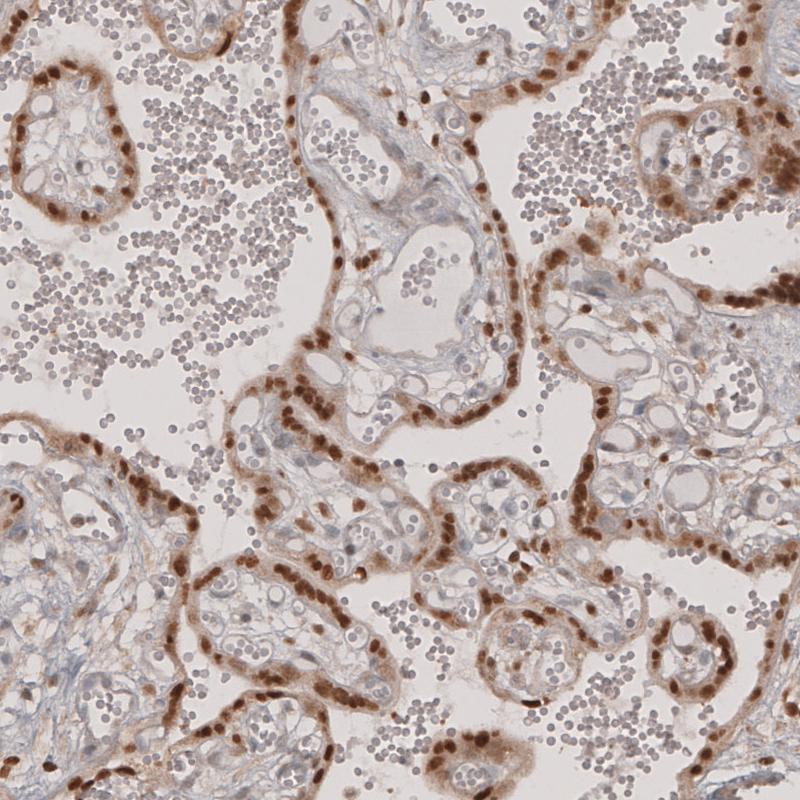

Immunohistochemical staining of human placenta shows moderate to strong nuclear positivity in trophoblastic cells.